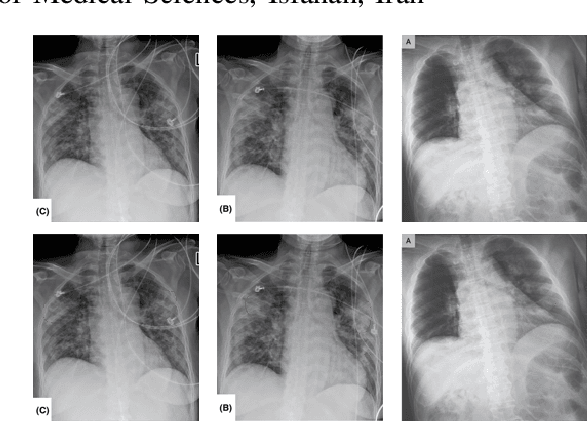

Abstract:The COVID-19 pandemic is causing a major outbreak in more than 150 countries around the world, having a severe impact on the health and life of many people globally. One of the crucial step in fighting COVID-19 is the ability to detect the infected patients early enough, and put them under special care. Detecting this disease from radiography and radiology images is perhaps one of the fastest way to diagnose the patients. Some of the early studies showed specific abnormalities in the chest radiograms of patients infected with COVID-19. Inspired by earlier works, we study the application of deep learning models to detect COVID-19 patients from their chest radiography images. We first prepare a dataset of 5,000 Chest X-rays from the publicly available datasets. Images exhibiting COVID-19 disease presence were identified by board-certified radiologist. Transfer learning on a subset of 2,000 radiograms was used to train four popular convolutional neural networks, including ResNet18, ResNet50, SqueezeNet, and DenseNet-121, to identify COVID-19 disease in the analyzed chest X-ray images. We evaluated these models on the remaining 3,000 images, and most of these networks achieved a sensitivity rate of 97\%($\pm$ 5\%), while having a specificity rate of around 90\%. While the achieved performance is very encouraging, further analysis is required on a larger set of COVID-19 images, to have a more reliable estimation of accuracy rates. Besides sensitivity and specificity rates, we also present the receiver operating characteristic (ROC), area under the curve (AUC), and confusion matrix of each model. The dataset, model implementations (in PyTorch), and evaluations, are all made publicly available for research community, here: https://github.com/shervinmin/DeepCovid.git